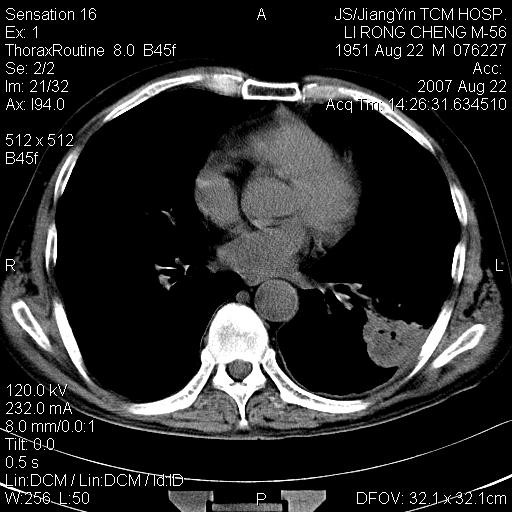

标题: CT9479:M,56Y,DM病史,咳嗽发热5天.肺脓疡.肺癌? [打印本页]

标题: CT9479:M,56Y,DM病史,咳嗽发热5天.肺脓疡.肺癌?

边灶边缘较光整,冠状位病灶呈大片状,,内有空洞,有胸膜反应,但无明显胸膜外侵犯征像,结合病史支持考虑肺肿脓,不排除结核,治疗后复查

好多钙化灶哦,病灶位于下叶背段,或许考虑结核更合适,做下相应检查先

左肺下叶见类软组织密度影,其内密度不均,有小空洞,广基与胸膜相连,其周见斑片状致密影.

考虑肺肿脓,不排除结核.

左肺下叶支气管呈小囊状扩张。下叶背段有类圆形高密度影,边缘模糊,外与胸膜相连。左侧胸膜增厚粘连。心包膜增厚。结合病史考虑1支扩并感染2胸膜及心包炎。

左下肺团片状类软组织密度影,形态不规则,边缘欠规整,其内可见液化区及气体影,病灶内侧见引流支气管影,相邻胸膜反应性增厚。病灶周围肺野内见增粗支气管,壁厚,边缘模糊。考虑:支气管扩张并感染;肺脓肿。